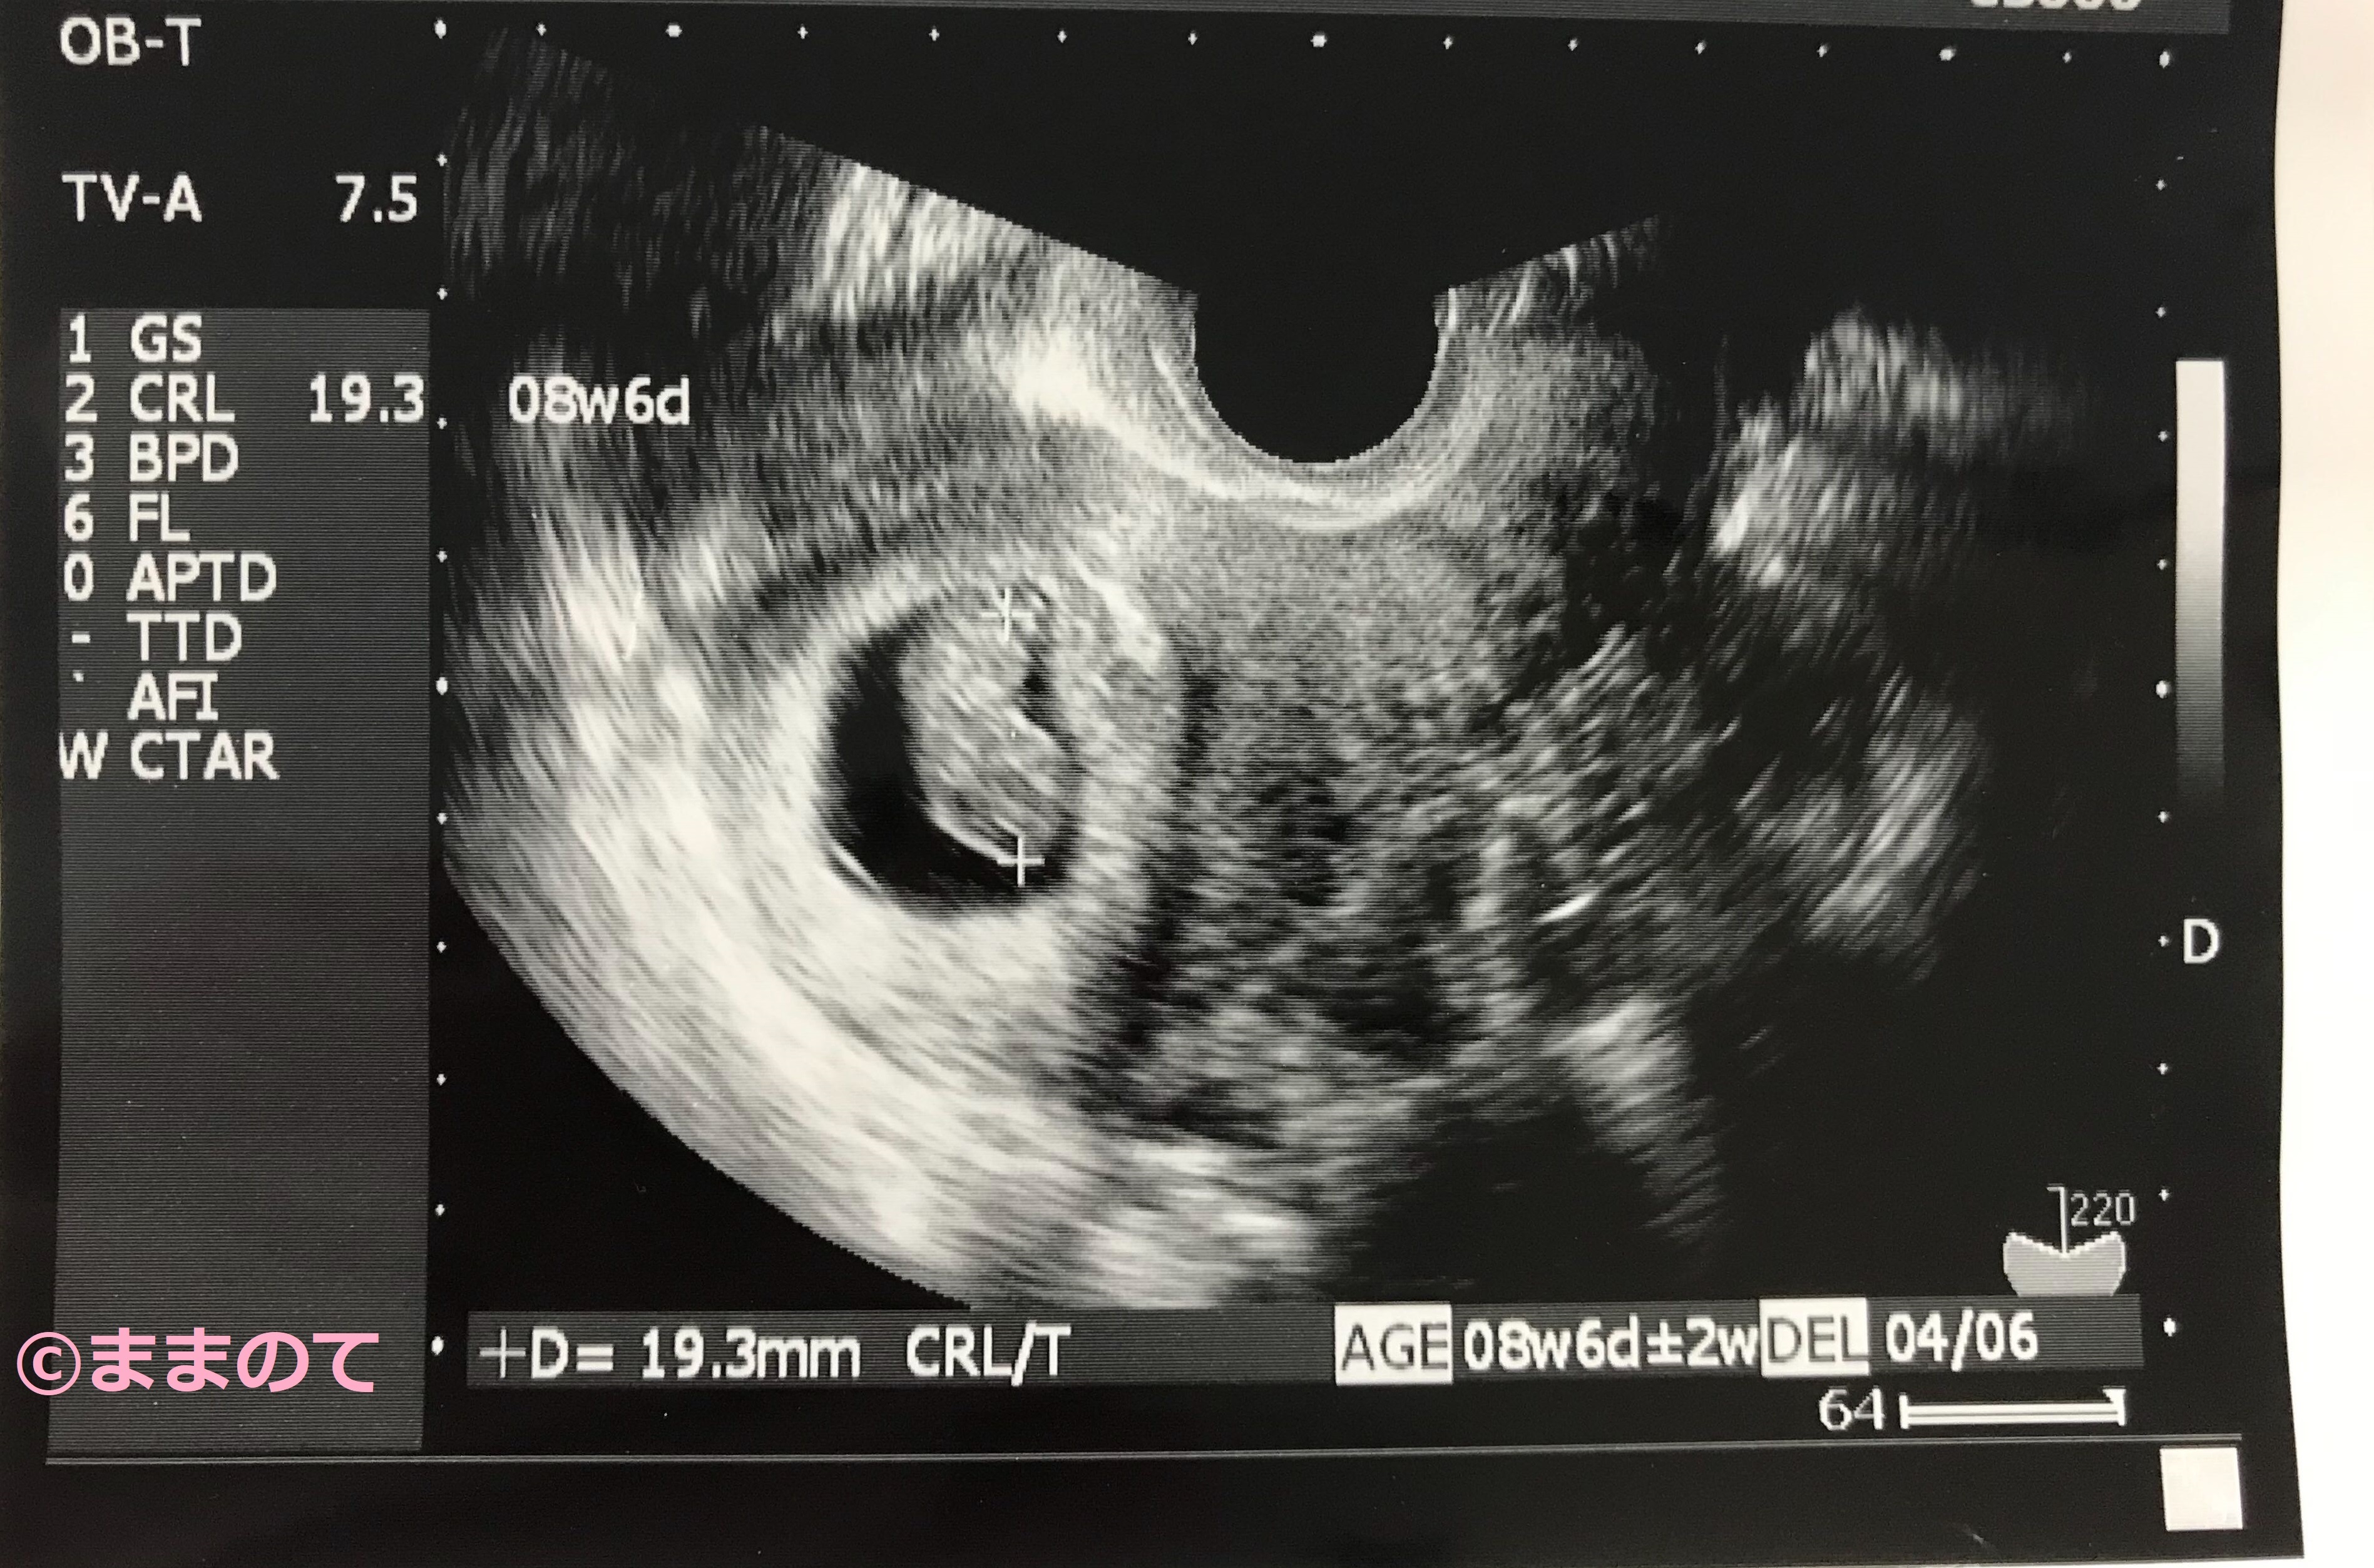

妊娠8週の赤ちゃんのエコー画像

妊娠8週6日のエコー画像です。2頭身になっていることがわかりますね。

妊娠8週のエコー検査では赤ちゃんの頭殿長(とうでんちょう)を測ります。頭殿長とは赤ちゃんの頭からおしりまでの大きさのことです。CRLと表記されることもありますよ。妊娠8~10週の赤ちゃんの大きさは個体差が少ないため、この時期のCRLの値によって出産予定日が正確に決まります。